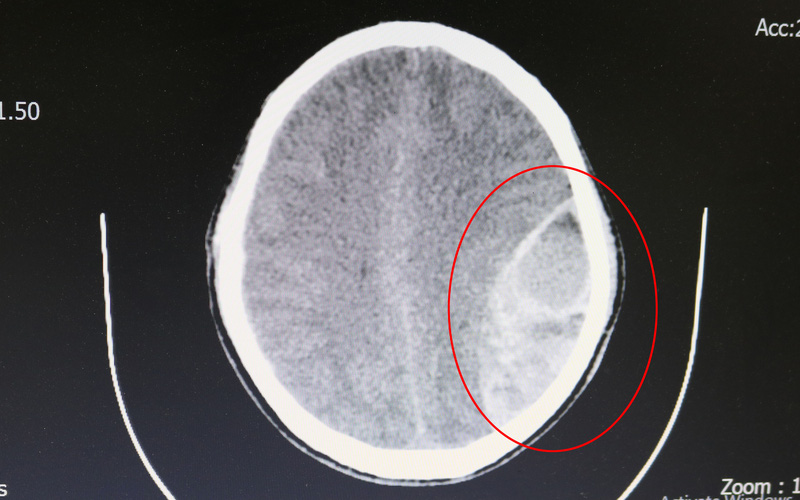

Theo BSCKI. Lê Văn Hiếu, Phó Trưởng khoa Ngoại thần kinh cho biết: Khi nhập viện người bệnh đã hôn mê, đồng tử trái giãn tối đa. Trên hình ảnh Chụp CT-Sanner sọ não cho thấy có khối máu tụ ngoài màng cứng thái dương trái số lượng nhiều.